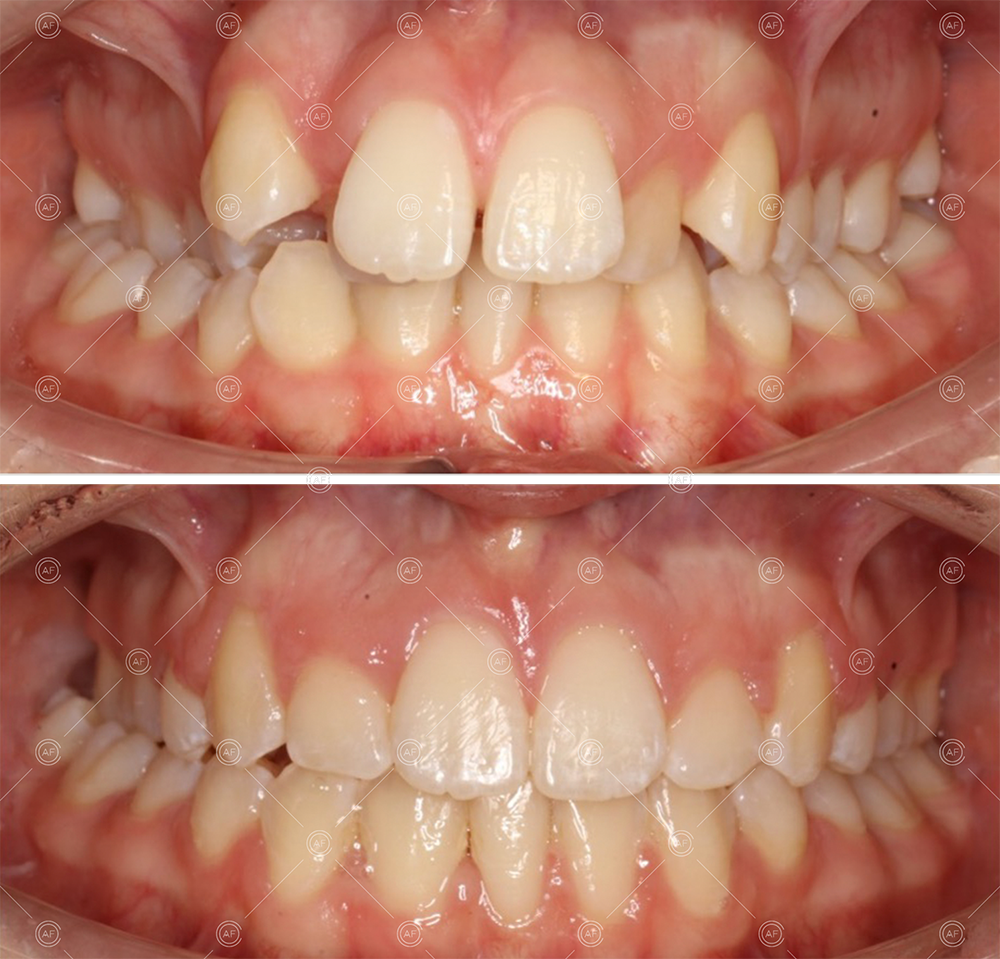

After careful treatment planning, the following treatment plan was formulated:

- Oral hygiene to an exemplary standard

- Extraction of upper right 5, upper left 4, lower left 5, lower right 5

- Fixed appliances in the upper and lower arches

The aim of the treatment was to relieve upper and lower arch crowding, correct lower centre line shift, treat class 1 incisors and buccal segments.